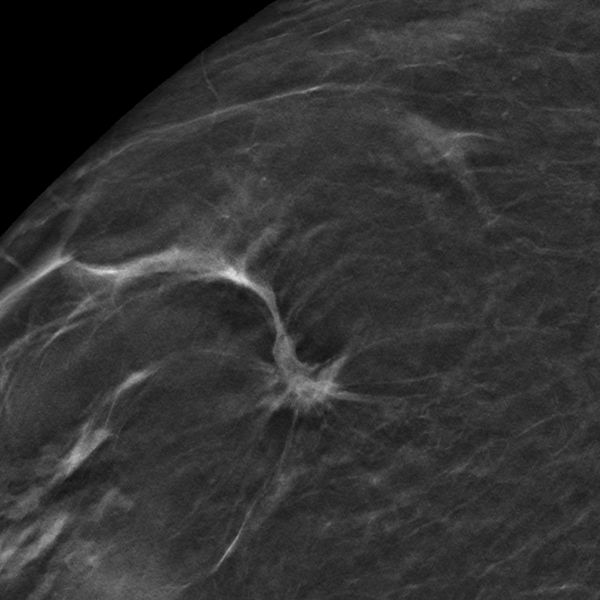

Systematische Brustkrebs-Früherkennung mit Digitaler Brust-Tomosynthese (DBT) und synthetischer 2D-Mammographie. (Quelle: Referenzzentrum Mammographie Münster)

Die Universitätsradiologie Münster erforscht innovative Bildgebungstechniken und deren Auswirkung auf die Effizienz der Brustkrebs-Früherkennung. In der ToSyMa-Studie wurde die Digitale Brust-Tomosynthese (DBT) – eine Weiterentwicklung der digitalen Mammographie – in Kombination mit so genannten synthetischen 2D-Mammogrammen, mit dem bisherigen Screening-Standard verglichen. Erste Ergebnisse der Studienphase 1 sind aktuell in The Lancet Oncology erschienen. Darin ist die Annahme bestätigt worden, dass Brustkrebs mit der weiterentwickelten Mammographie-Technik signifikant häufiger als mit der Standard-Mammographie entdeckt wird. Der Grund: Der innovative Bildgebungsansatz reduziert die Wahrscheinlichkeit, dass überlappende Gewebestrukturen radiologische Zeichen für Malignität verdecken.

Die Deutsche Forschungsgemeinschaft (DFG) fördert die Studie mit mehr als 1,6 Mio. Euro bis in das Jahr 2025. Die DFG unterstützt damit das Ziel, die Frühdiagnostik von Brustkrebs weiter zu optimieren. Die Weiterentwicklung der digitalen Mammographie zur Brust-Tomosynthese bietet eine Technologie, die durch die Berechnung von Pseudo-3D-Datensätzen potentielle Gewebeüberlagerungen in der Brust reduziert und daher diagnostische Vorteile verspricht.